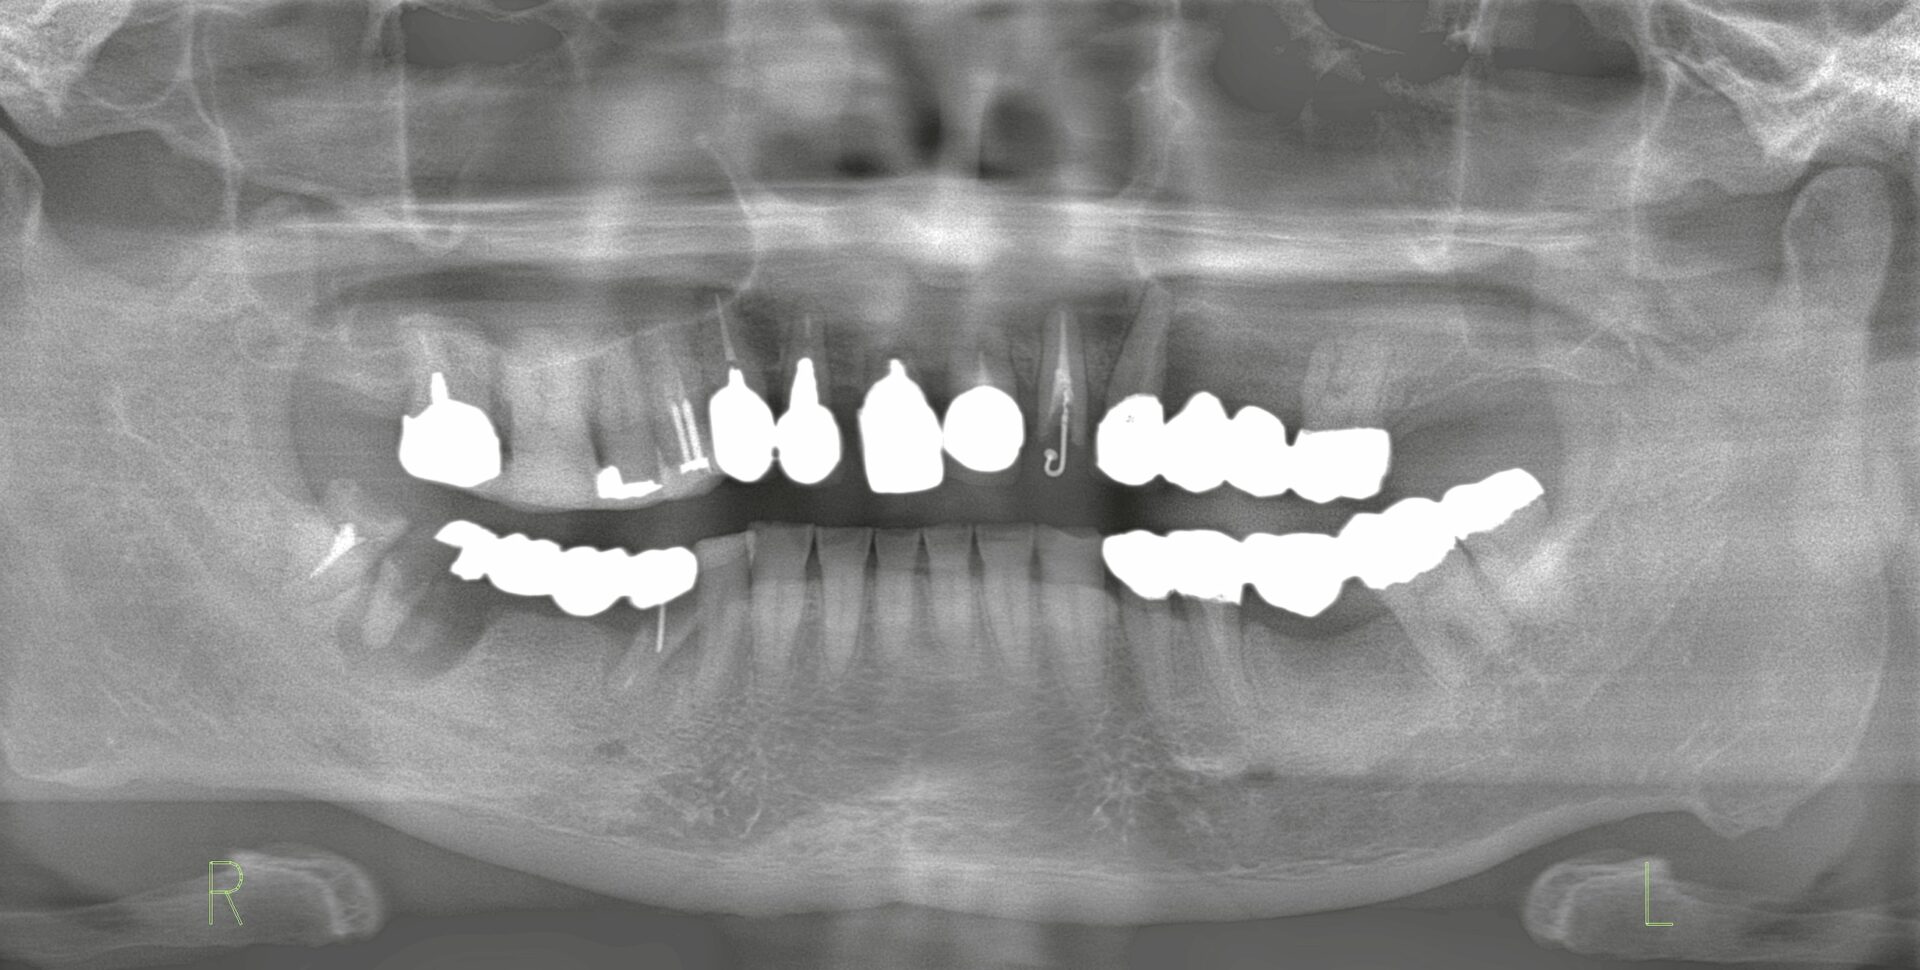

| Details | Chief complaint しっかり噛めなくなってきた |

| 術前写真 |

| Treatment plan | 1. 不適合クラウンの除去 2. 右下保存不可部の抜歯+骨造成 → インプラント2本埋入 3. 上顎前歯部の抜歯 → インプラント4本埋入 4. 左下ブリッジの除去 → インプラント埋入 |

患者様は強い咬合力を有しており、特に習慣的なウエイトトレーニングの影響から、食いしばりによる負担が著明でした。 そのため、 * 奥歯の崩壊に伴い前歯部へ突き上げが集中 * 前歯の歯根吸収および歯根破折を引き起こした 従来型のブリッジなどでは再度破折を招く可能性が高いため、インプラント治療による欠損補綴を選択しました。 補綴設計は、奥歯の咬合支持回復と前歯部の突き上げを分散することを目的としました。 |